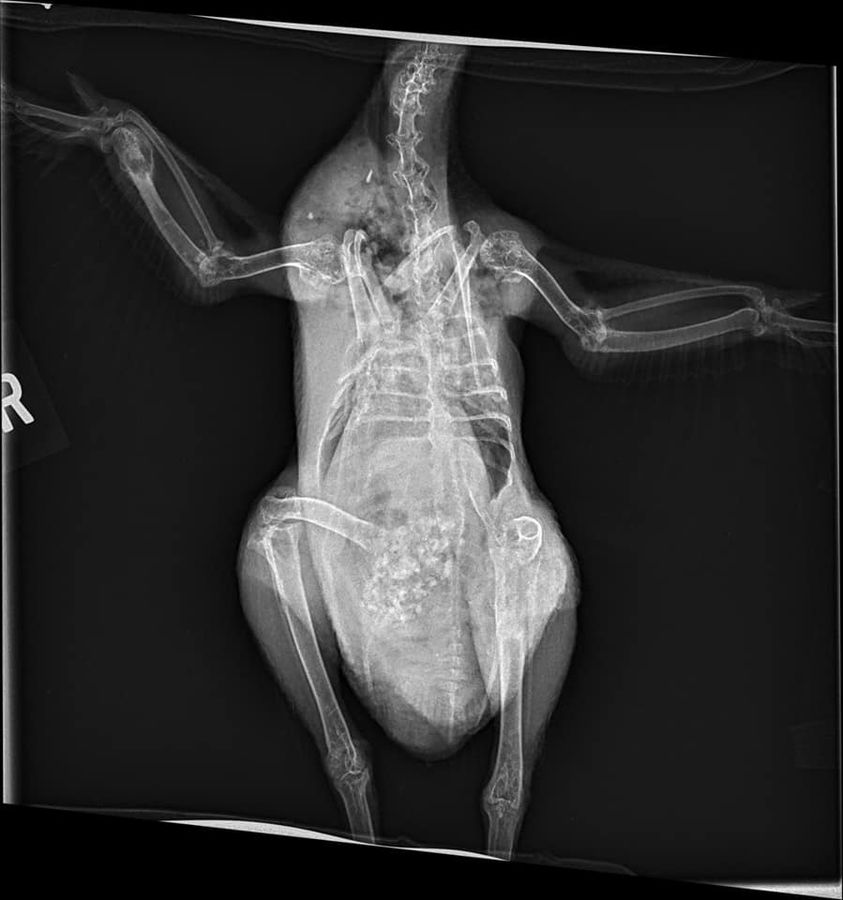

“Our Silkie hen has had a limp that has been getting worse over the last year. The vet took x-rays and sent them to a specialist who diagnosed a bone cyst in her leg and on her wing. She is now on Metacam, but we’re unsure where to go from here. The vet says we could do a biopsy of the cyst, but that would be in the $600-700 dollar range and we can’t afford that right now.”

Dr Bowes: The areas of deterioration in the wing and hip are not bone cysts. Osteosarcoma is one condition that eats bones, but is rare. Avian Tuberculosis is another possibility, but this case is more likely to be linked to bacterial arthritis caused by a Staphylococcus infection. There are multiple sites of deterioration in the wing (distal ulna) and no bone articulation in the hip making it increasingly difficult for the hen to walk. Recommendation: humane euthanasia.